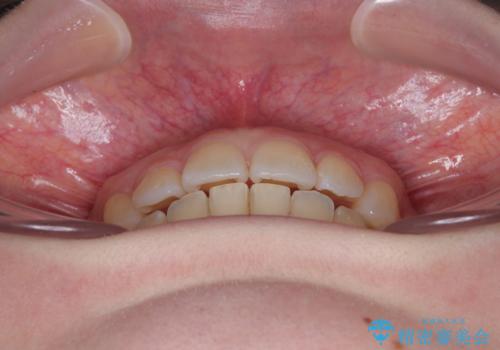

- 左上の前歯が出ていることを主訴として来院された患者様です。

1年と少しで矯正治療を終えることができ患者様は大変満足されました。